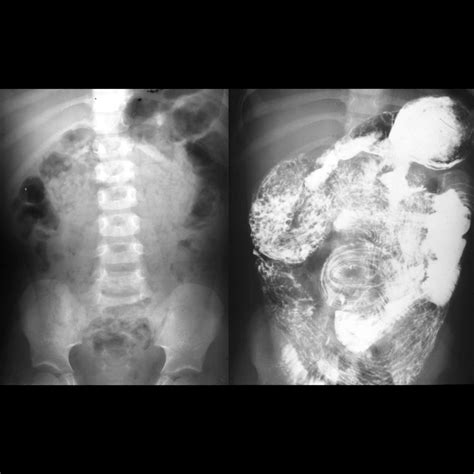

The actual Small Bowel Follow Through typically takes between one to four hours, depending on how quickly your digestive system moves the barium. Here is what you can expect during your appointment:

Initial Scout Film The radiologist takes an initial X-ray of your abdomen to ensure the bowel is clear.

Barium Intake You will drink a cup of barium sulfate, which is often flavored to make it more palatable.

Serial Imaging The technician will take X-ray images at specific intervals (usually every 15 to 30 minutes) as the contrast travels through your system.

Monitoring You may be asked to lay on your side or stomach to help the barium move along the intestine.

Final Evaluation Once the contrast reaches the cecum (the beginning of the large intestine), the study is considered complete.